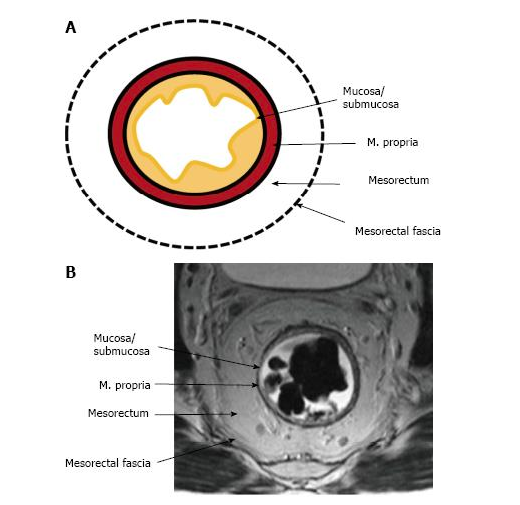

Hình ảnh trực tràng trên cộng hưởng từ:

+ Lớp dịch nhầy: giảm tín hiệu ở T1w, tăng tín hiệu ở T2w.

+ Lớp niêm mạc: là lớp rất mỏng, nhận biết dựa trên hình ảnh của lớp dịch nhầy láng trên bề mặt niêm mạc và lớp dưới niêm mạc.

+ Lớp dưới niêm mạc: tăng nhẹ tín hiệu cả ở T1w, T2w và rất ngấm thuốc.

+ Lớp cơ: giảm tín hiệu cả T1w và T2w đặc biệt cơ thắt trong rất giảm tín hiệu.

+ Lớp mỡ mạc treo trực tràng: tăng tín hiệu cả T1w và T2w.

+ Lớp cân mạc treo trực tràng hoặc thanh mạc: là lớp rất mỏng, nhận biết dựa trên hình ảnh lớp cơ và lớp mỡ cân mạc treo trực tràng.

+ Hệ xương: vỏ xương mất tín hiệu cả T1w và T2w.

Hình 1. Các lớp giải phẫu của trực tràng tương ứng trên cộng hưởng từ